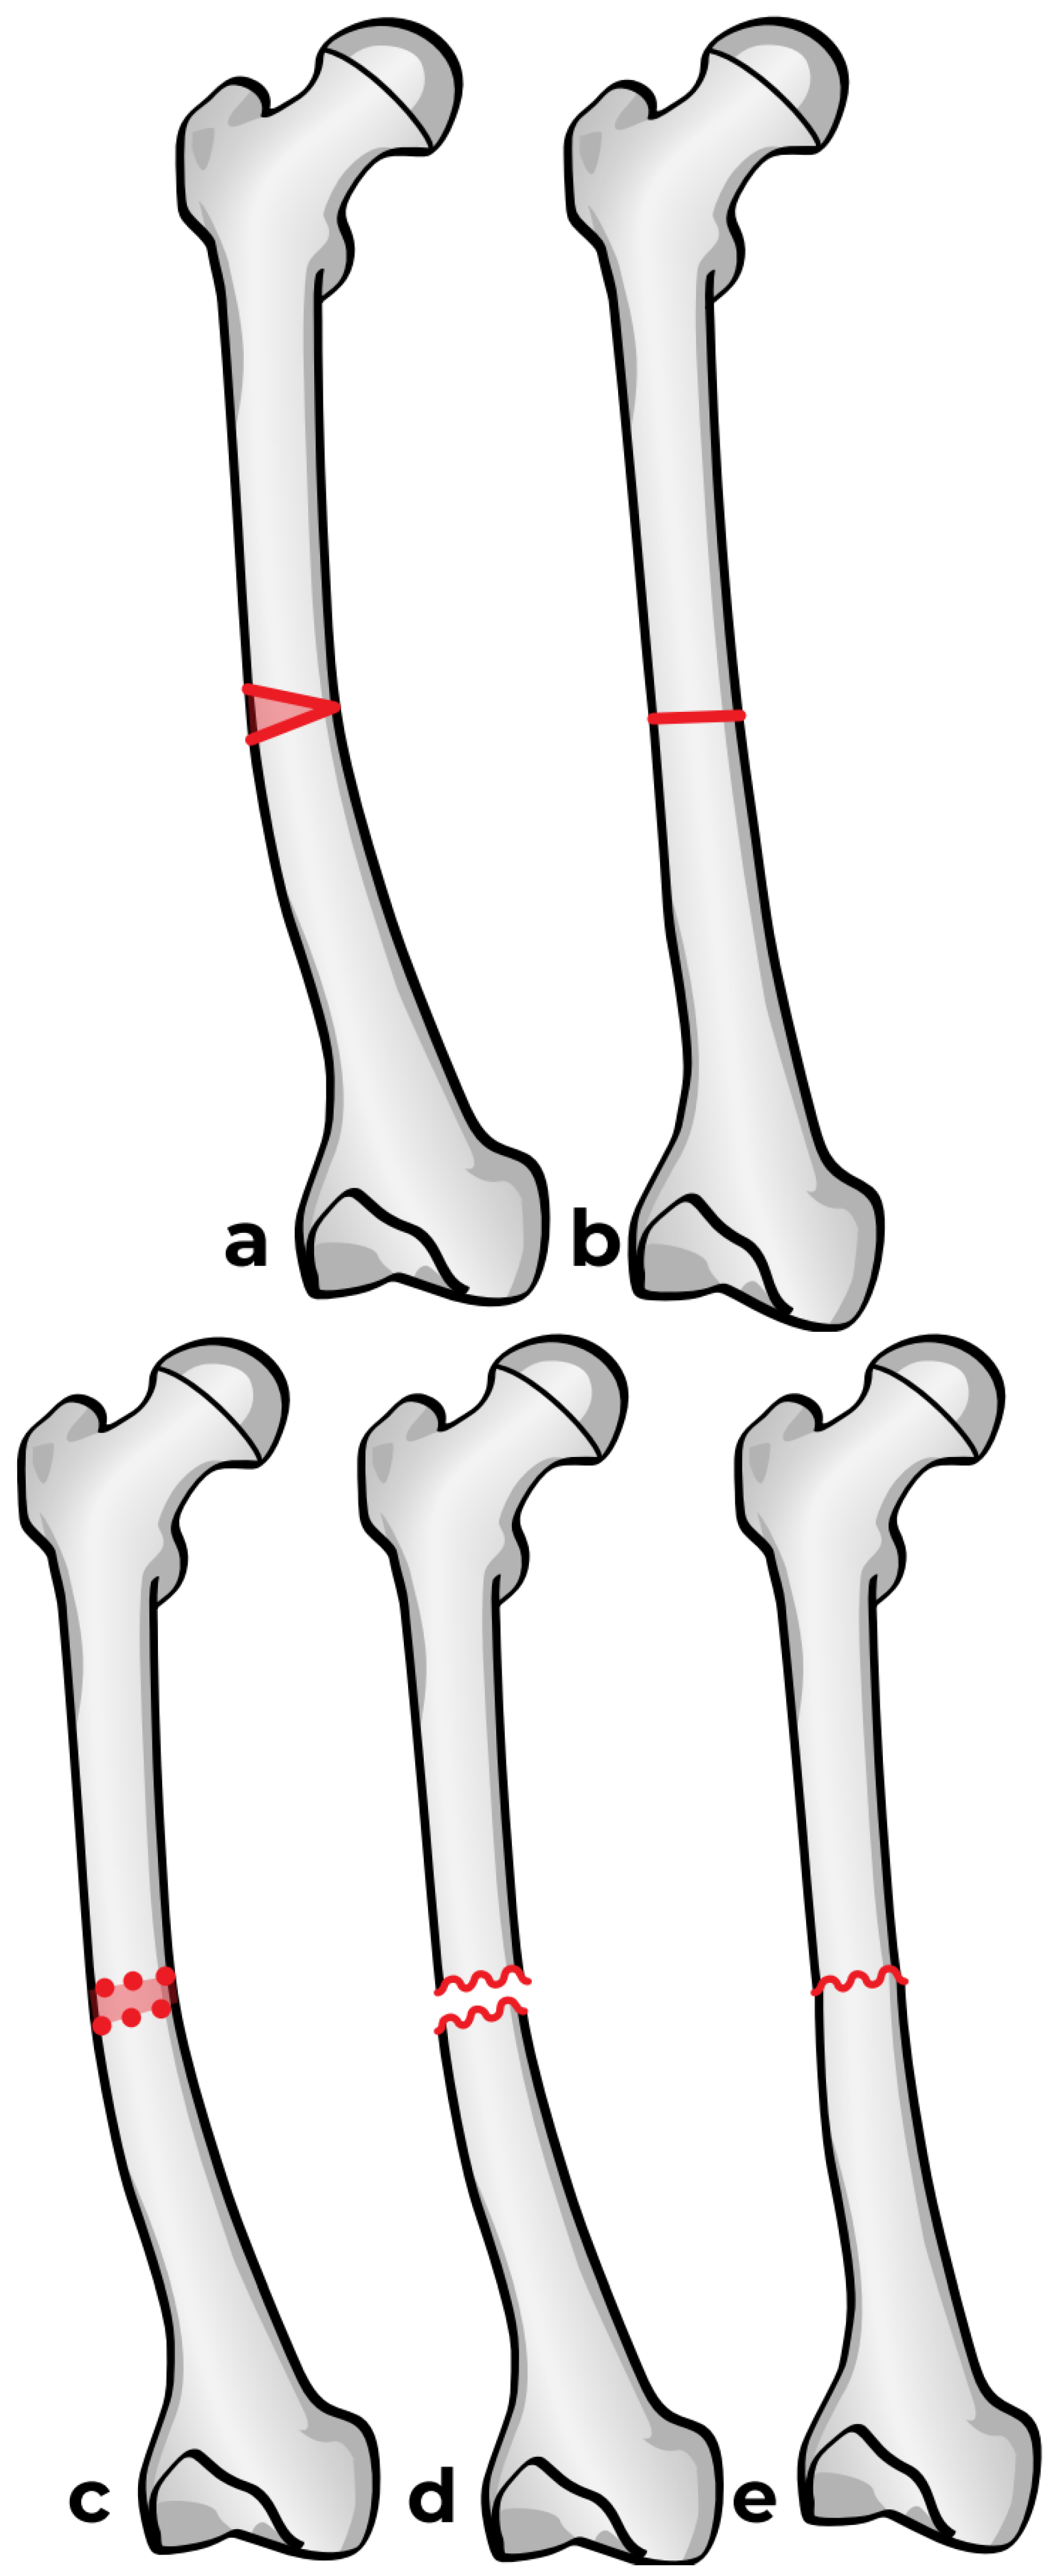

Figure 6. Osteotomy Techniques. a-b: Osteotomy using an oscillating saw. c-e: Osteotomy using multiple drill holes and an osteotome.

Two options are available: the first one is a straight-cut osteotomy using an oscillating saw, which creates a smooth planar surface on either side (Figure 6a). This method, however, provides minimal rotational stability once the bone segments are reduced (Figure 6b). Furthermore, the thermal injury generated by the power saw may have a negative effect on bone healing at the osteotomy site. To address these limitations, we used a multiple drill hole osteotomy technique, in which closely spaced drill holes are made along the planned osteotomy plane before making the cut (Figure 6c). This results in opposing surfaces being rugged and not smooth (Figure 6d). This interdigitation acts as a mechanical interlock between the bone fragments once reduced, which offers some rotational stability and reduces the need for fixation hardware (Figure 6e).